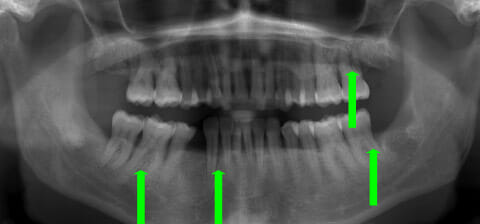

Panoramica prima e dopo la terapia parodontale con laser e microscopio

Con terapia parodontale fotodinamica non chirurgica: si noti la ricrescita naturale dell’osso e del tessuto parodontale.